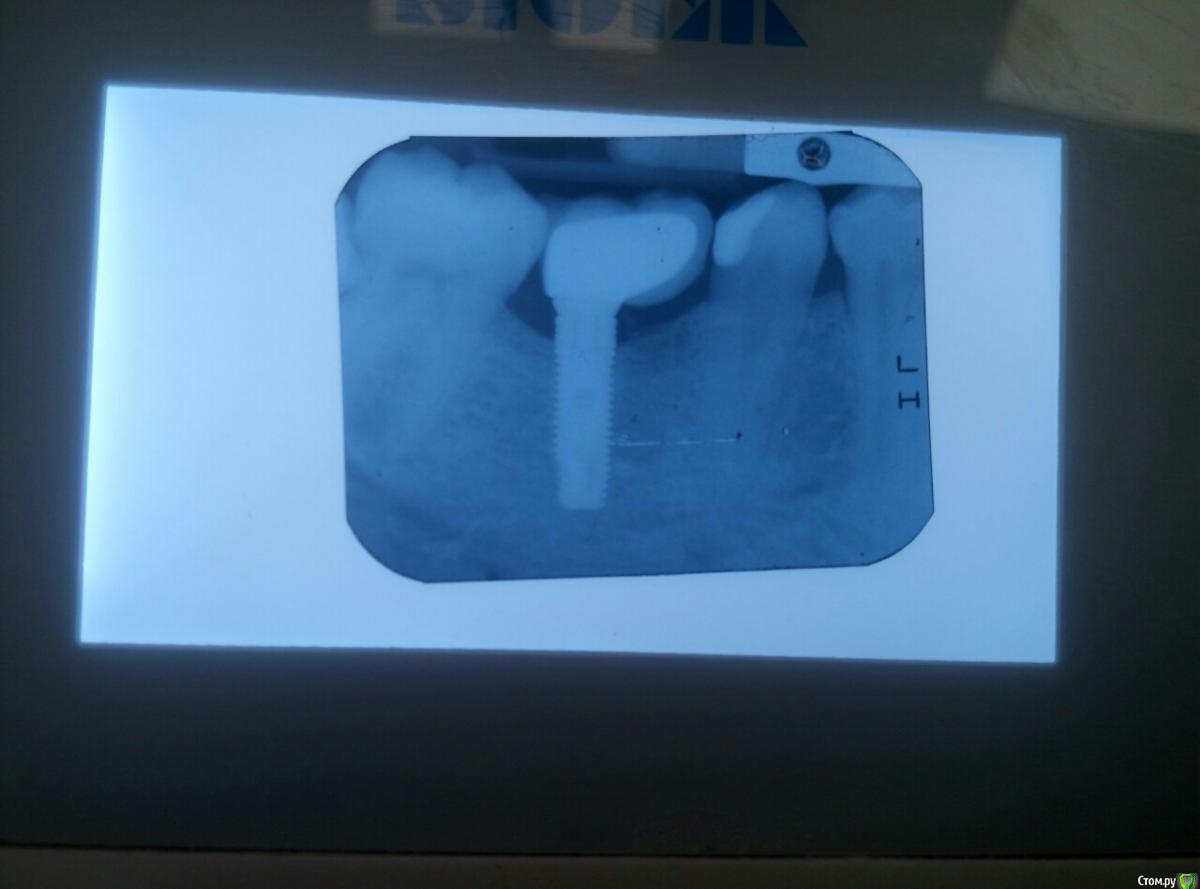

Norton Опубликовано 28 августа, 2016 Поделиться Опубликовано 28 августа, 2016 Доброго времени суток уважаемые коллеги! Прошу помощи советом.В первом случае установлен имплант Альфа Био 4.2*13 12 мес. назад, коронка была установлена 8 мес. назад. Биотип тонкий, прикрепленная есть но мало. Жалобы пациента на забивание пищи под имплант. Имплант установлен не совсем так как хотелось.Во вором случае был установлен имплант Необиотек 4.5*11.5 8 мес. назад, коронка была установлена 4 мес. назад. Прикрепленной также мало. Жалобы пациента на забивание пищи под имплант. Как и в первой ситуации имплант установлен не так как хотелось, у пац. плохо с открыванием рта (коротких фрез на тот момент еще не было). Варианты решения:В первом случае изготовить новую коронку на индивидуальном абатменте.Во втором случае удалить 38, установить дополнительный имплант медиальнее, изготовить новую коронку. Ссылка на комментарий

Аслан Опубликовано 29 августа, 2016 Поделиться Опубликовано 29 августа, 2016 странно. мне кажется или там недосели коронки? ну и по позиции имплантов. 47 при плохом открывании рта поставили с дистальным наклоном, а 36 с медиальным... я за переустановку и сразу с сст. 1 Ссылка на комментарий

Доктор Хаус Опубликовано 30 августа, 2016 Поделиться Опубликовано 30 августа, 2016 Платформы имплантатов слишком коронарно располагаются . С десной работать надо будет в любом случае ( при замене имплантатов или при оставлении этих) . При таких широких промежутках я бы протезировал только на винтовой фиксации. Ссылка на комментарий

dentikl Опубликовано 2 сентября, 2016 Поделиться Опубликовано 2 сентября, 2016 мне кажеться под 46 мезиально что-то осталось, похожее на цемент Ссылка на комментарий